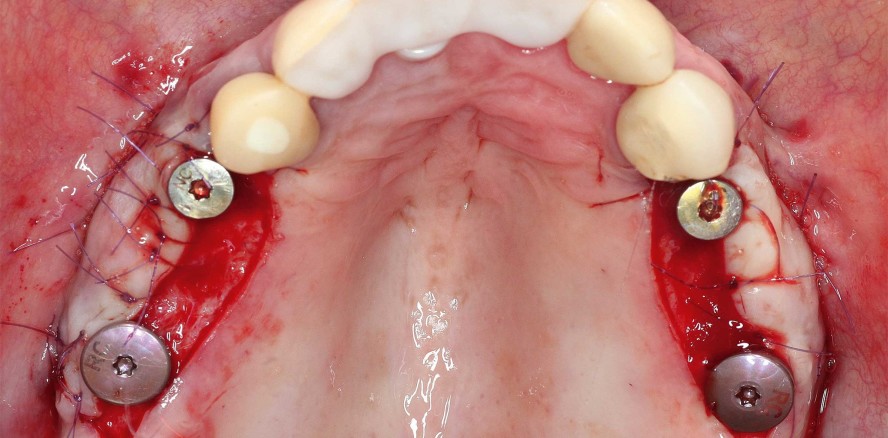

Im nächsten Schritt wurde die prothetische Versorgung beider Kiefer eingeleitet. Durch den Hauszahnarzt wurde die begleitende parodontologische und konservierende Therapie umgesetzt. Um im atrophierten Kiefer eine implantatgetragene prothetische Versorgung realisieren zu können, wurde ebenfalls durch den Hauzahnarzt ein Knochenaufbau durchgeführt. Nach einer mehrmonatigen Einheilphase wurden im November 2020 die Implantate (insgesamt fünf im Oberkiefer, zwei im Unterkiefer) inseriert (Abb. 4). Für ein optimales Weichgewebsmanagement kam im Unterkiefer ein Bindegewebstransplantat zum Einsatz. Die Platten wurden auf Wunsch der Patientin belassen. Anschließend erfolgte die prothetische Versorgung mit festsitzendem Zahnersatz im Ober- und Unterkiefer (Abb. 7d–f).